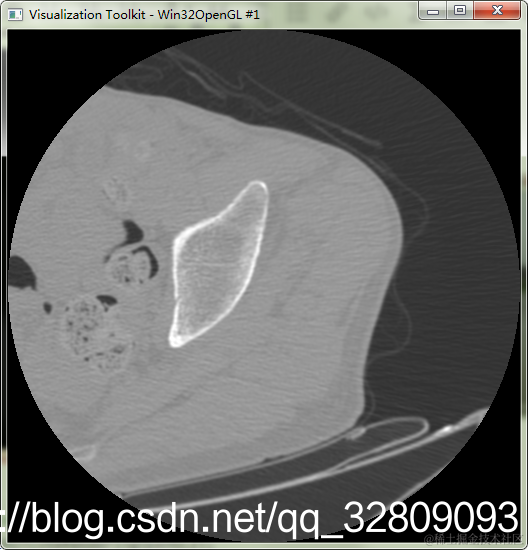

实例14:读取DCM医学图像并显示

在这里插入图片描述

#include "vtkAutoInit.h"

鼠标左键按住不放,上下移动调整窗位,左右移动调整窗宽